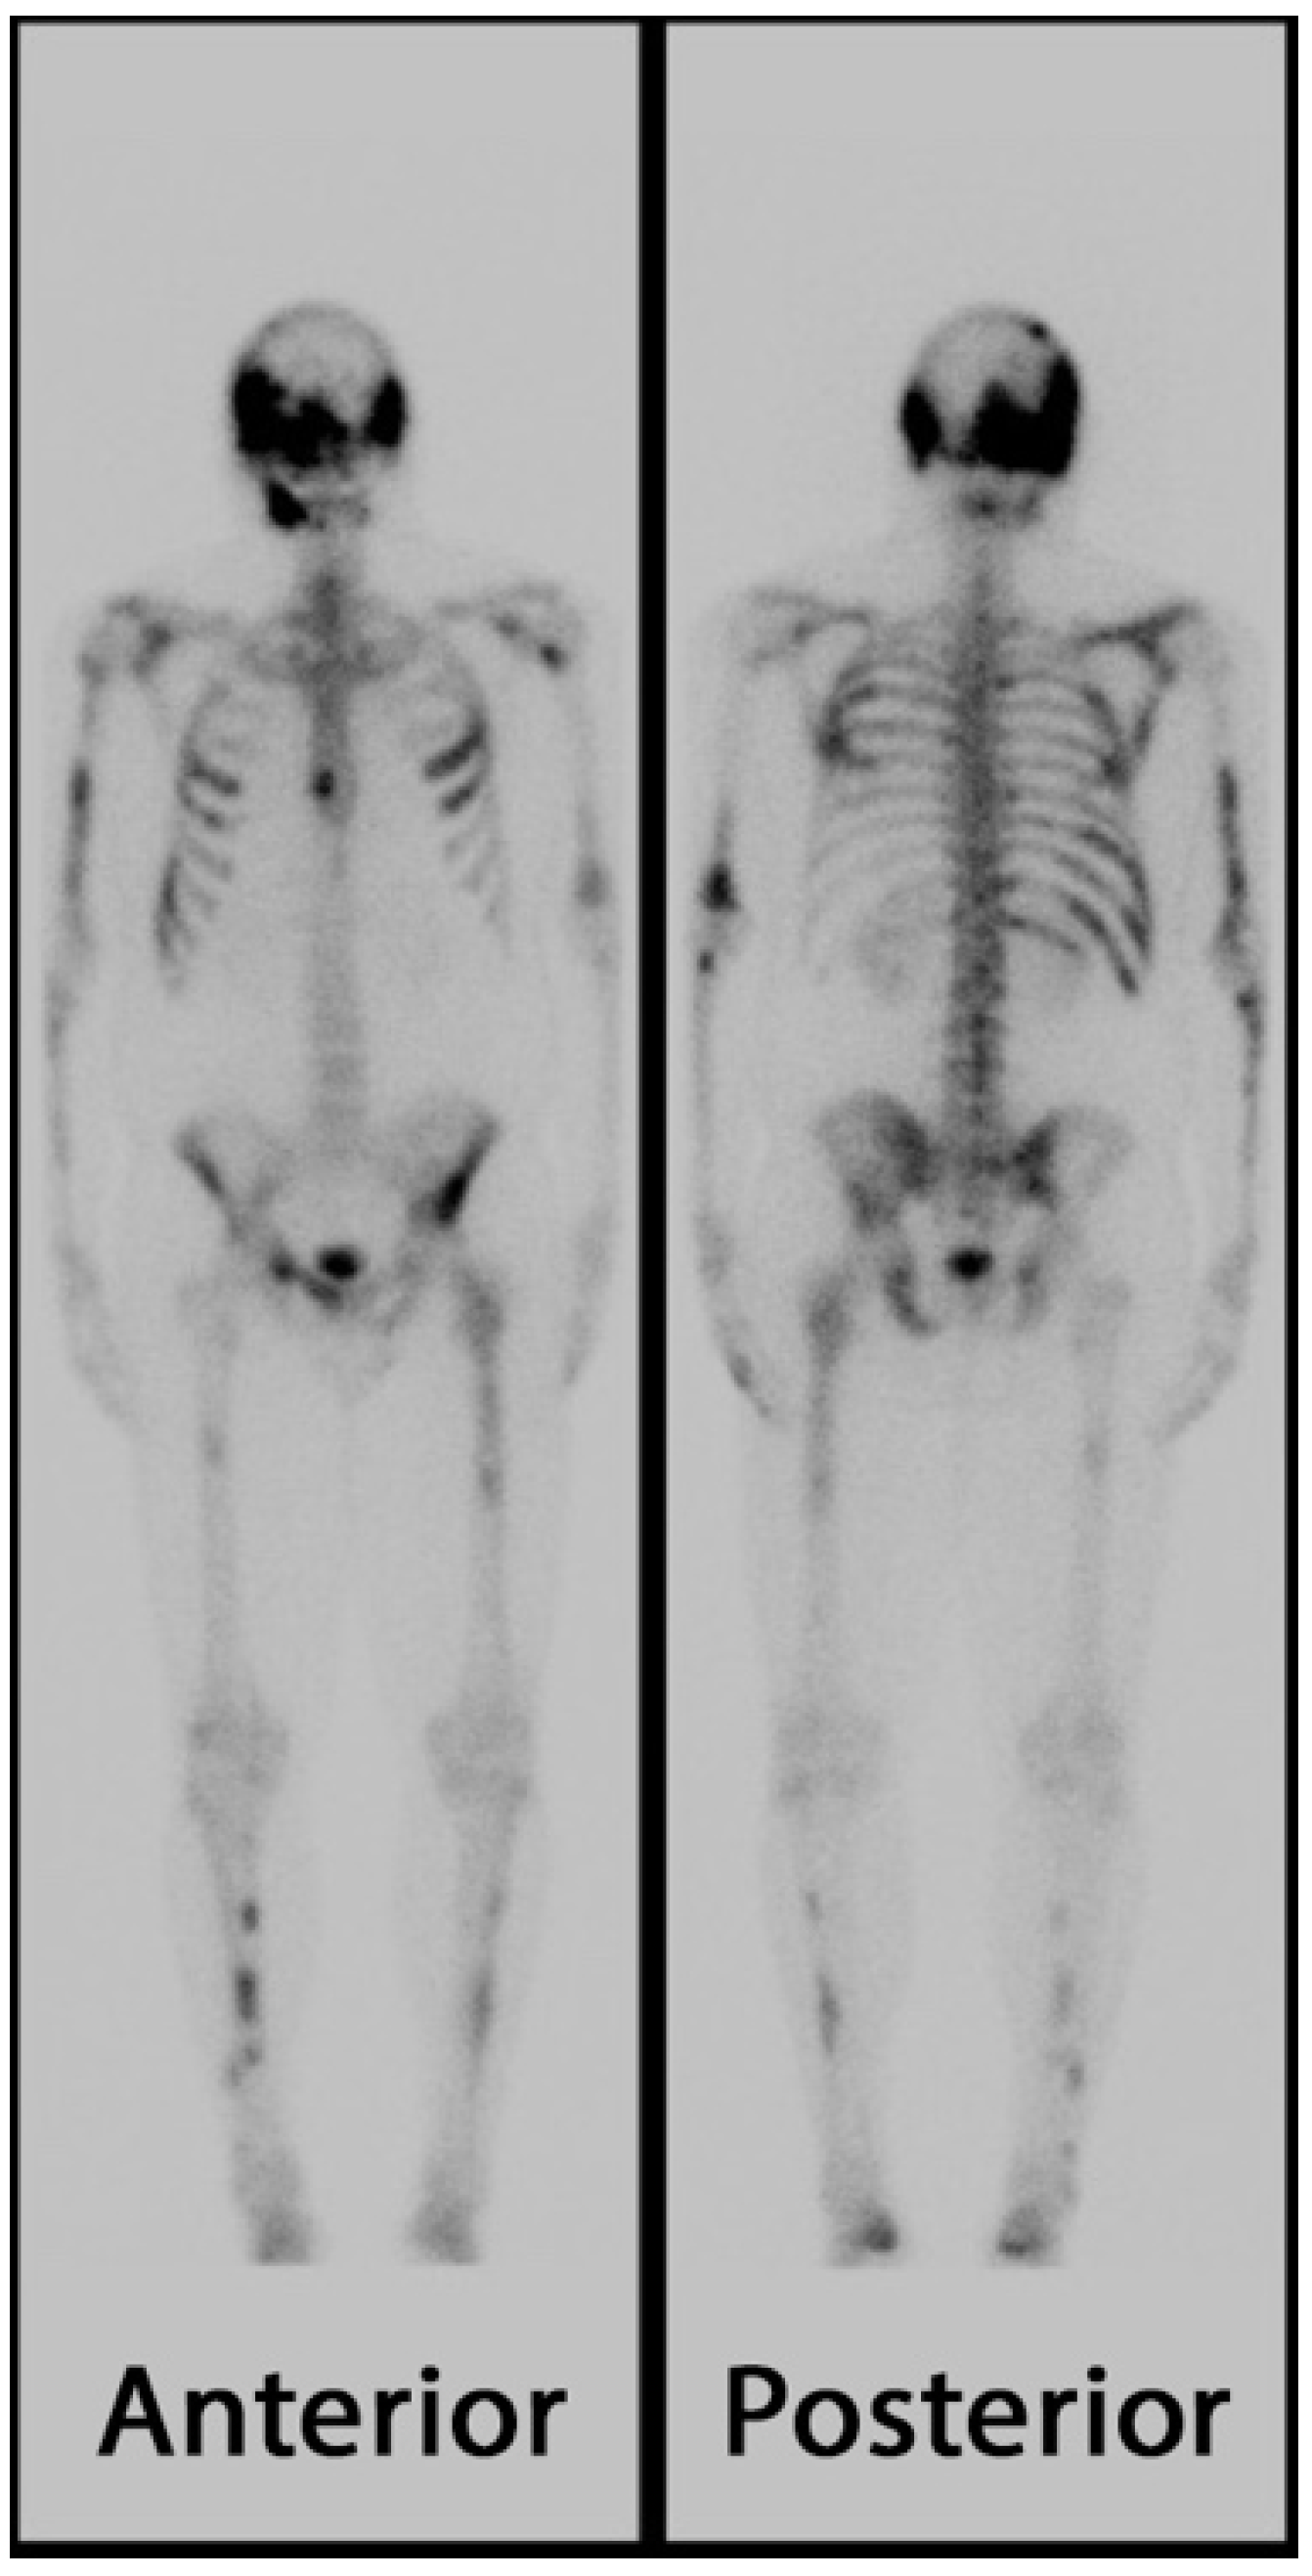

3. Skeletal Manifestations of FD/MAS

3.1. Appendicular Manifestations of FD/MAS

3.2. Axial/Craniofacial Manifestations of FD/MAS

- Hart, E.S.; Kelly, M.H.; Brillante, B.; Chen, C.C.; Ziran, N.; Lee, J.S.; Feuillan, P.; Leet, A.I.; Kushner, H.; Robey, P.G.; et al. Onset, progression, and plateau of skeletal lesions in fibrous dysplasia and the relationship to functional outcome. J. Bone Miner. Res. 2007, 22, 1468–1474. [Google Scholar] [CrossRef]